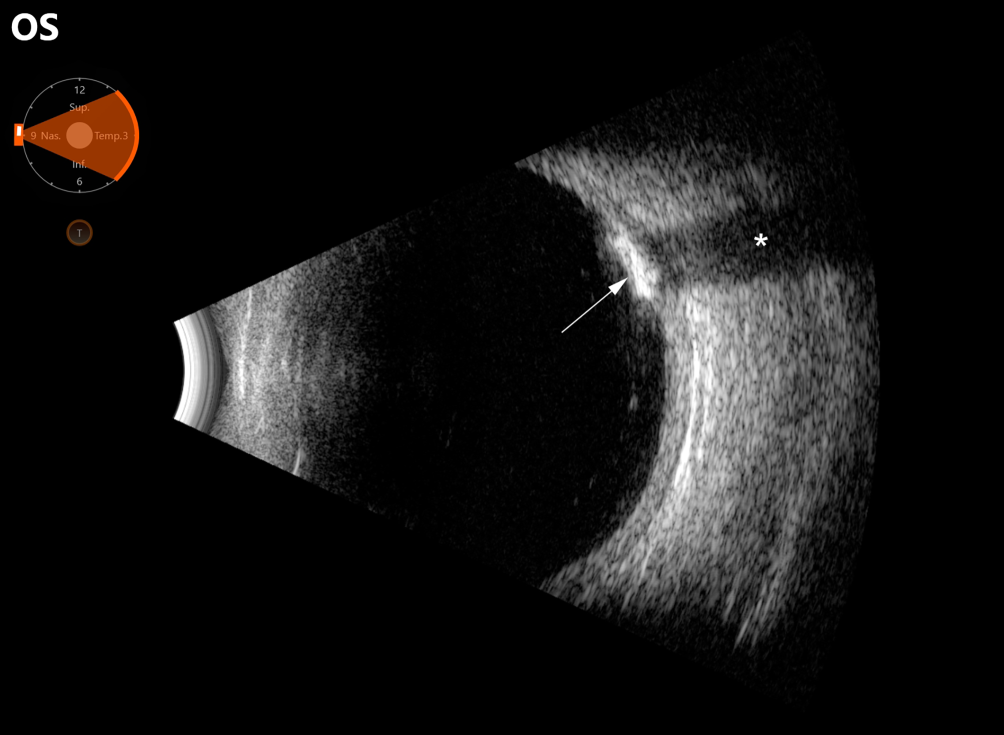

Abb. 3

Sonographie des linken Auges. Die Läsion stellt sich als hyperechogene Struktur (Pfeil) mit distaler Schallauslöschung (Sternchen) dar. Eine retrobulbäre Raumforderung ist nicht sichtbar

In der optischen Kohärenztomographie (OCT) waren die Befunde für Papille und Makula beidseits unauffällig. Die Papillen waren auch in der Heidelberg Retina Tomographie (HRT) unauffällig. Im Januar 2021 und 2022 wurde jeweils eine Gesichtsfelduntersuchung durchgeführt (Abb. 2), welche jeweils frei sowohl von glaukomatösen als auch den Läsionen korrespondierenden Defekten waren. Die Mean Deviation (MD) betrug am rechten Auge −0,5 dB, am linken Auge −0,4 dB. In der Sonographie zeigten sich die Läsionen als hyperechogene sklerochoroidale Strukturen mit distaler Schallauslöschung (Abb. 3) ohne Hinweis auf eine retrobulbäre Raumforderung. In der Fundusautofluoreszenz (Abb. 1, A2, B2) zeigten sich die Läsionen als hyperfluoreszierende Areale. In der Enhanced-Depth-Imaging-OCT (EDI-OCT) sind die betroffenen Netzhautareale unauffällig, die Choroidea erscheint aber leicht verdünnt (Abb. 4). Mittels internistischer Laboruntersuchung (u. a. Blutbild, Elektrolyte, Leber- und Nierenwerte, Entzündungsparameter und Blutgerinnung) konnte eine systemische Beteiligung ausgeschlossen werden.

Die sklerochoroidale Kalzifizierung ist eine seltene Erkrankung, welche meist als Zufallsbefund während einer Routineuntersuchung beim niedergelassenen Augenarzt bei älteren Patienten diagnostiziert wird [5]. Im Allgemeinen sind die Patienten beschwerdefrei, und die Sehschärfe ist nicht herabgesetzt, da sich die Läsionen in der Peripherie befinden und die Fovea aussparen. Es wurden jedoch schon Fälle beschrieben, in denen auch der N. opticus betroffen ist, was zu einer progredienten und schweren bilateralen Sehverschlechterung führen kann [6]. Die Klassifizierung kann anhand des morphologischen Erscheinungsmuster in der EDI-OCT erfolgen [1]. Die Läsionen sind charakteristisch bilateral vorhanden, auch wenn es manchmal schwierig sein kann, diese fundoskopisch zu detektieren, insbesondere wenn die Läsionen weit in der Peripherie liegen. Hier kann die Sonographie – und als Ultima Ratio die Computertomographie – hilfreich sein, da die Läsionen hier als hyperdense Raumforderung sichtbar werden [4].